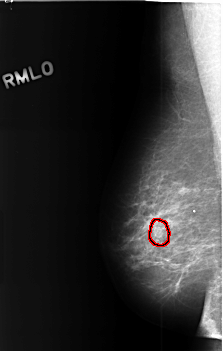

C_0450_1.RIGHT_MLO

FILE: C_0450_1.RIGHT_MLO.OVERLAY

TOTAL_ABNORMALITIES 1

ABNORMALITY 1

LESION_TYPE MASS SHAPE OVAL MARGINS CIRCUMSCRIBED

ASSESSMENT 3

SUBTLETY 4

PATHOLOGY BENIGN_WITHOUT_CALLBACK

TOTAL_OUTLINES 1

BOUNDARY